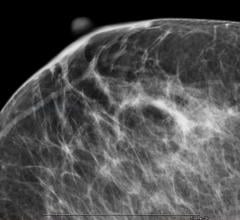

Mammography is a breast imaging technique that uses X-rays to diagnose and locate tumors of the breasts.

Dense breast tissue can mask the appearance of tumors and limit the performance of mammography. When used as an adjunct ...